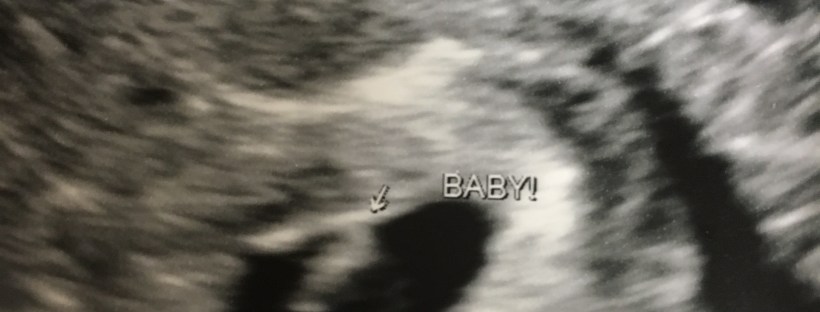

We got to see our incredible miracle for the first time on Wednesday morning. It was beautiful 🙂 He or she was completely unrecognizable as a baby at this point, but beautiful nonetheless! And do you know what the most amazing thing was??? We could see our baby’s heartbeat!!! Yes, at 6 weeks 1 day, measuring just 5 mm, we could see the fluttering of their circulatory system! We could see they have life and energy flowing through them! We could see the awesome wonder that they already are on the screen in front of us! Breathtaking.

Lincoln came with to the appointment, excited to see his sibling. We had hoped to actually hear the heartbeat, but I guess it’s too early for that. We settled for seeing that amazing pulse and were able to measure the heart rate at 137!!! Lincoln was even speechless for a moment when he saw the flickering. He beamed with a proud smile for his strong brother or sister and quickly asked if it was a boy or girl. He’s convinced of and expecting {not hoping, expecting} a sister.